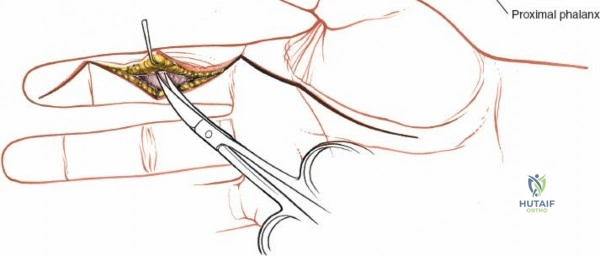

Surface landmarks guide the incision. In the digits, these include the distal phalangeal crease (just proximal to the distal interphalangeal joint), the proximal interphalangeal crease, and the metacarpophalangeal crease. In the palm, the distal palmar crease and thenar/hypothenar creases are important.

The skin incision must provide adequate exposure without creating straight lines across joint creases, which can lead to scar contracture. The Bruner zigzag incision is the standard for digital access due to its excellent exposure and prevention of flexion contractures. It incorporates the natural creases and extends proximally and distally in a zigzag fashion along the length of the digit. The apices of the V's are typically located over the mobile skin of the phalanges, avoiding the fixed skin over the joint creases.

- Finger Incision (Bruner): Begins dorsally/mid-laterally over the distal phalanx, angles volarly, crosses the volar skin crease, then angles back to the mid-lateral line, avoiding straight lines across joints. This allows creation of triangular skin flaps.

After marking the incision, the skin and subcutaneous tissues are carefully incised. In the digits, the triangular skin flaps created by the Bruner incision are elevated using fine skin hooks or small self-retaining retractors. Dissection should proceed in the subcutaneous plane, superficial to the digital neurovascular bundles, which run along the radial and ulnar borders of the digit, immediately adjacent to the flexor sheath.

Care must be taken to identify and protect these bundles. Any existing lacerations or hematomas are debrided. The digital nerves and vessels are carefully dissected free from the surrounding connective tissue and retracted, typically dorsally and laterally, using vessel loops or fine retractors to provide clear access to the underlying flexor sheath.

Fibrous Flexor Sheath Exposure

Once the subcutaneous tissue and neurovascular bundles are retracted, the fibrous flexor sheath is visible. This appears as a glistening white, tough structure enveloping the flexor tendons.